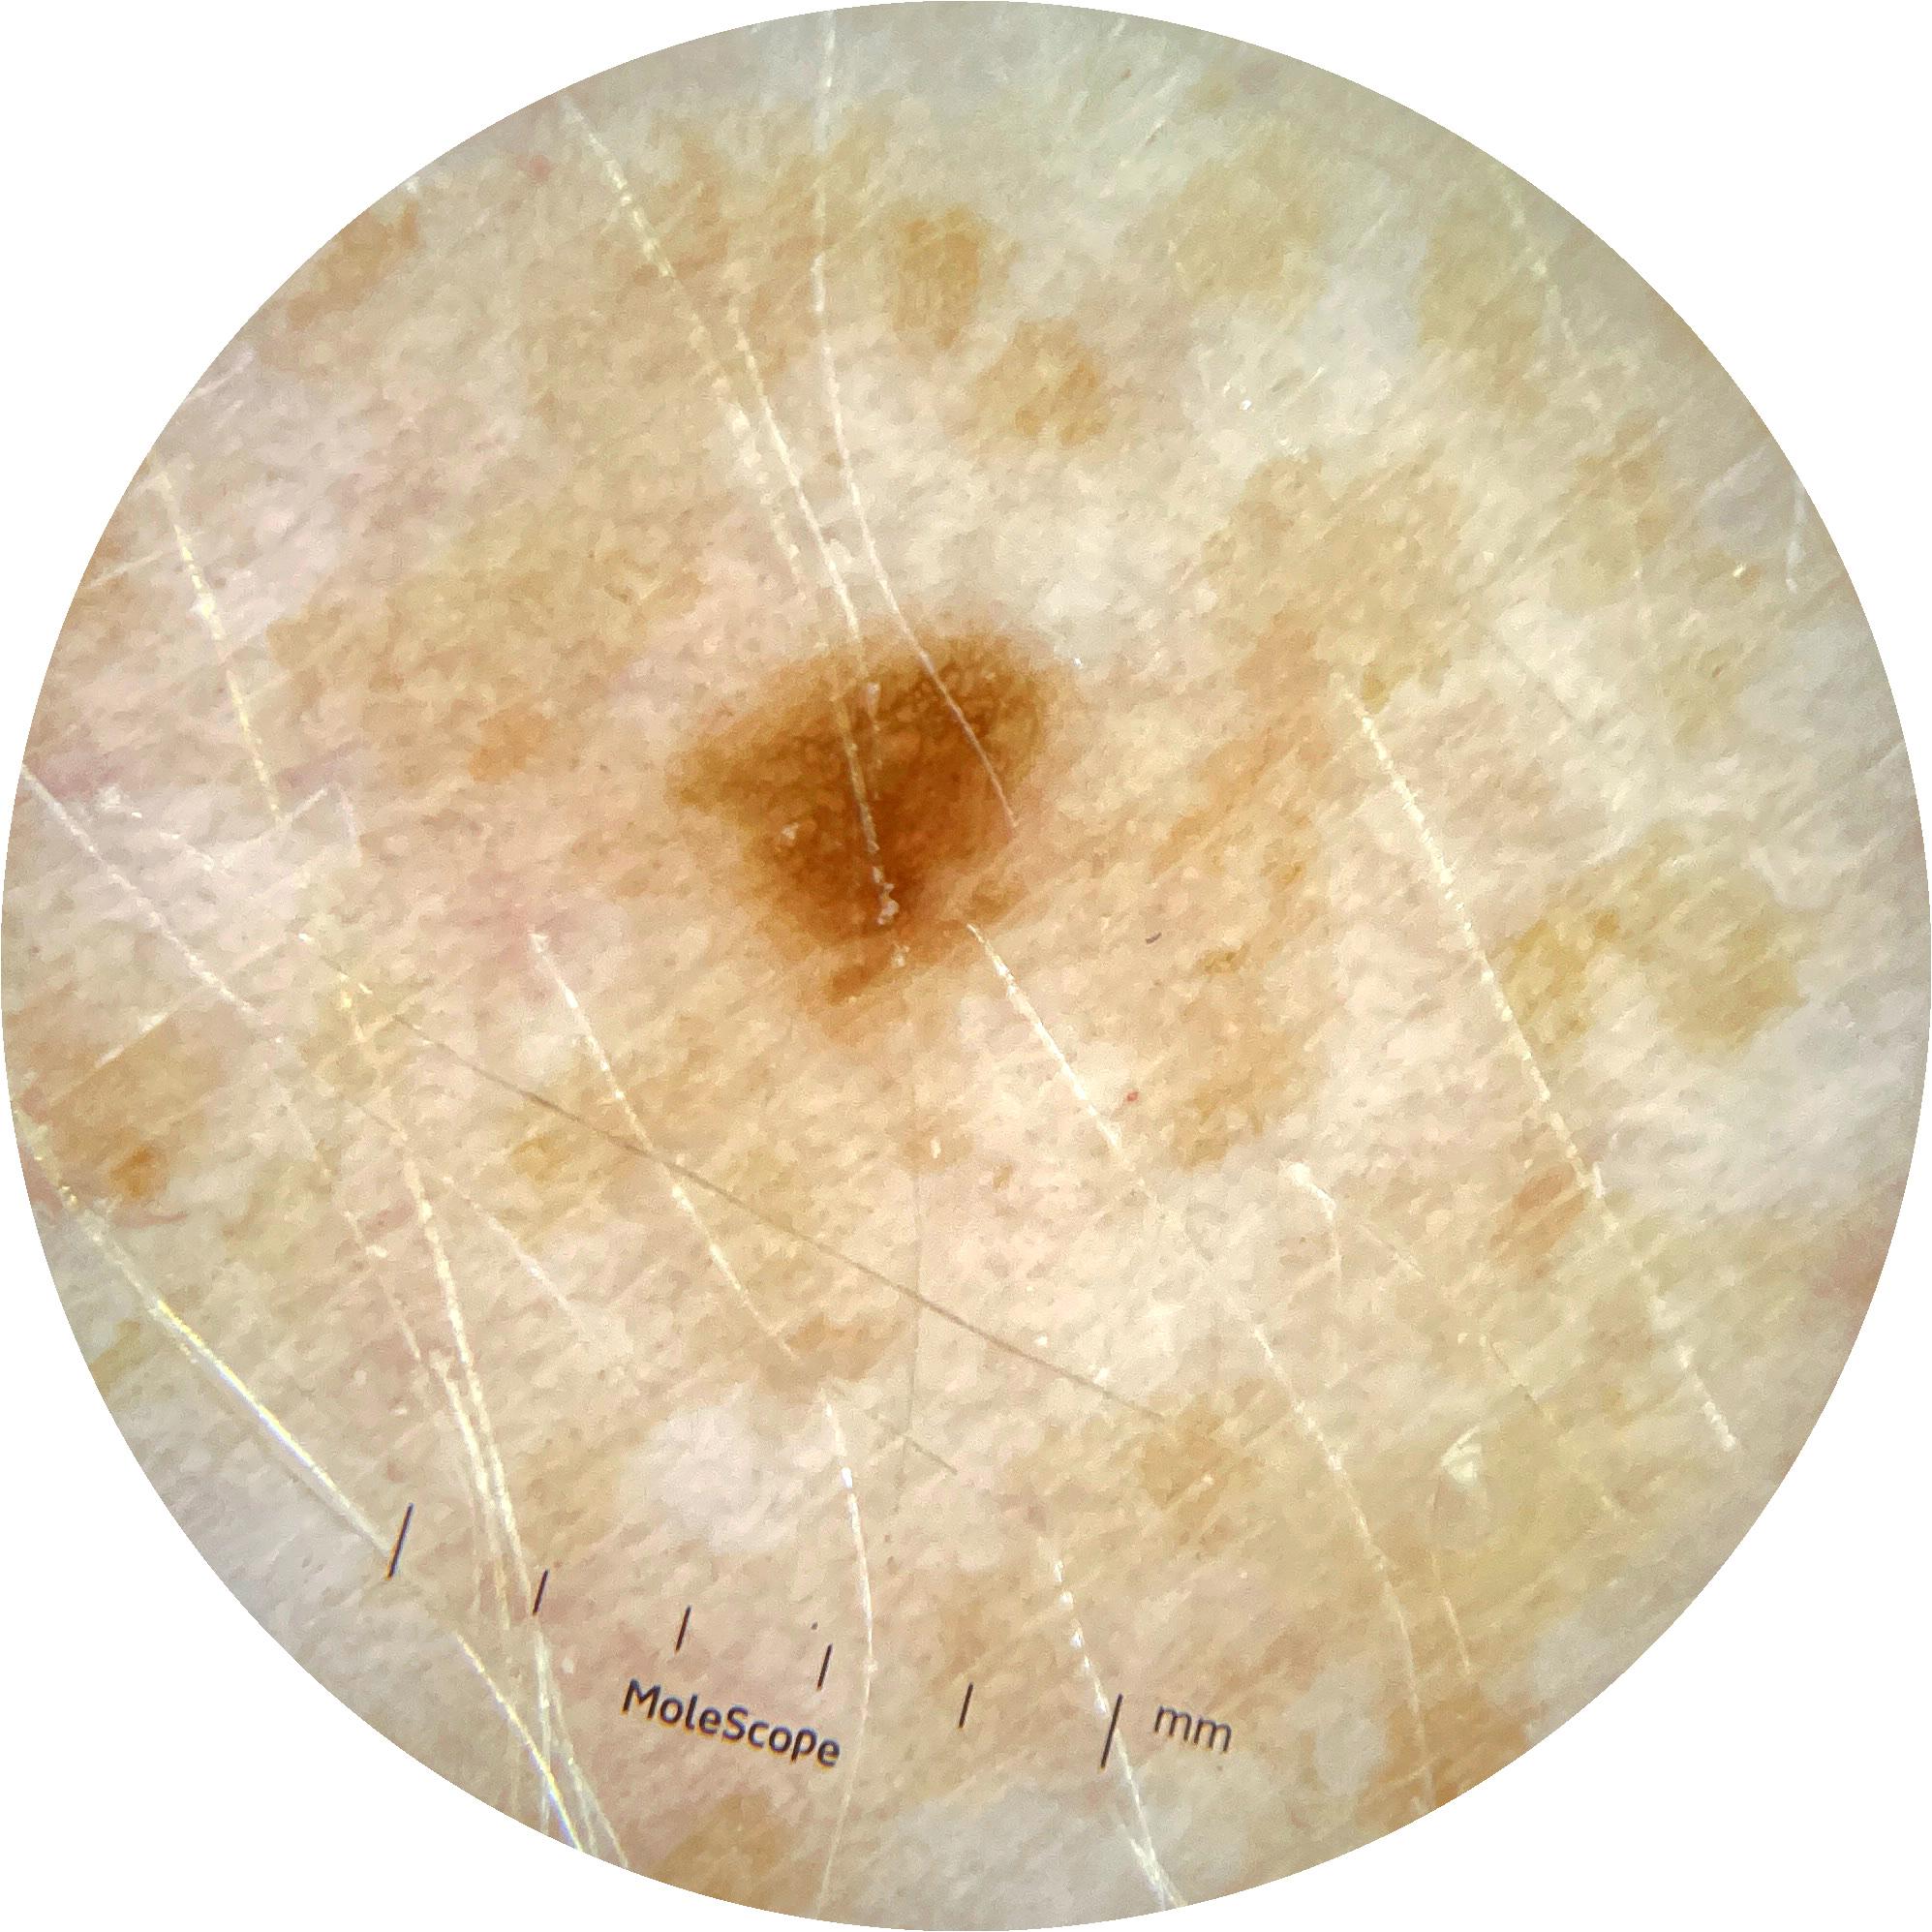

ISIC_9785574

2003 x 2003

Field Value

acquisition_day 148

age_approx 45

anatom_site_1 Head and neck

anatom_site_general head/neck

concomitant_biopsy False

diagnosis_1 Benign

diagnosis_confirm_type single image expert consensus

family_hx_mm True

image_manipulation instrument only

image_type dermoscopic

lesion_id IL_0236417

patient_id IP_8456088

personal_hx_mm True

sex female